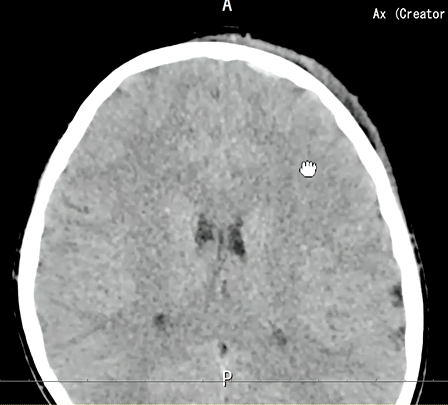

そして翌日、再度CT検査が行われました。

翌日の頭部CTで受傷部付近の画像です。

これを見て何か気づくことはないですか?

矢印の部位でわずかにここに出血があります。

軟部条件では観察しづらいのですが、WLを50、WWを100程度に設定すると、

わずかに高吸収域を認めます。外傷後の外傷性硬膜下出血と思われます。

もう1つ高吸収域が存在しています。

矢印の部位について、臨床の先生から”脳挫傷”があるのではないかと再読影の依頼が来ました。

受傷日と翌日のCTと比較すると、確かに出血が顕在化し、目立っておりわずかな硬膜下血腫もしくはくも膜下血腫と脳挫傷の可能性があると再読影をしました。